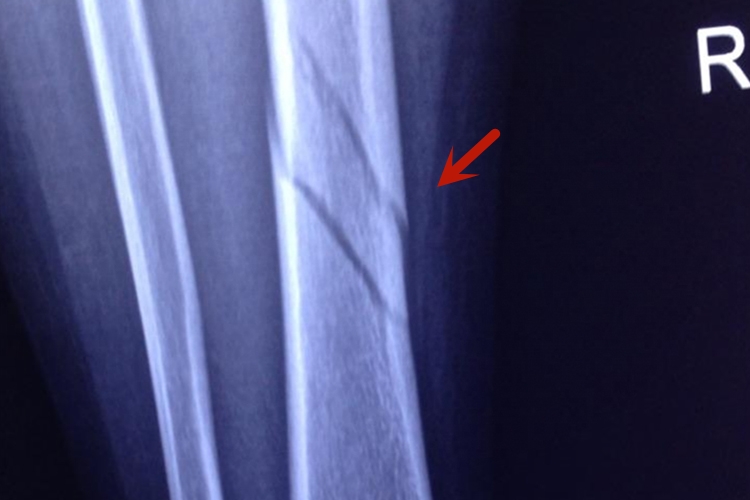

小腿胫骨腓骨骨折后,应及时进行处理,无移位的胫腓骨干骨折采用石膏固定,有移位的横形或短斜形骨折采用手法复位、石膏固定。恢复早期,骨折的局部血肿会产生初步的纤维连接,两周以后可形成骨痂。

小腿胫骨腓骨骨折后两周至三个月之间,随着骨痂生长、骨化以及骨质连接,可以逐渐达到骨折愈合。